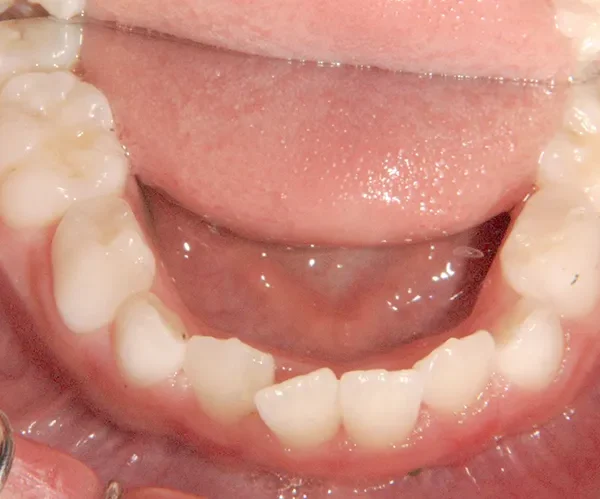

下の歯は永久歯の生えるスペースがないので、オリジナル矯正装置で受け口を治して、永久歯の生えるスペースを作りました。

治療回数19回、2年5ヶ月の治療期間で矯正治療を終了しました。

主訴が改善され、ご満足頂きました。

治療終了後